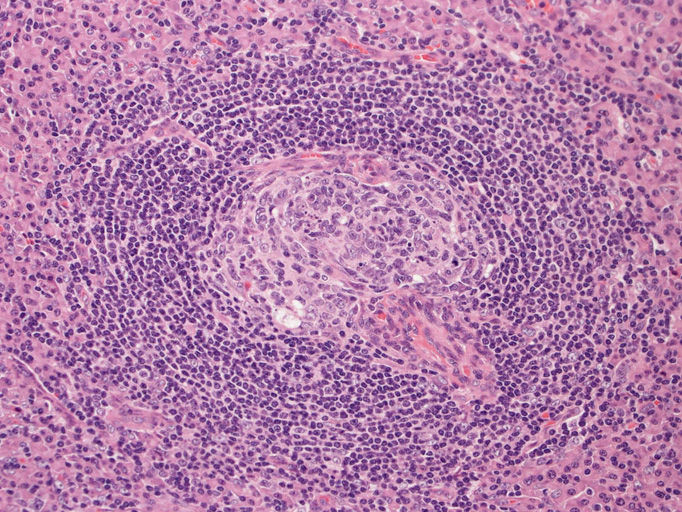

- 濾胞は小型で周囲を広いmantle zoneで囲まれている。同心円状のよく発達したmantle zoneは「onion skin」と呼ばれる。濾胞は濾胞樹状細胞と進入血管の内皮から構成されている。ときに大型奇異,「異形」細胞が見られるが異常な濾胞樹状細胞と考えられる。-> Dr. Castlemanが「Hodgkin diseaseとの鑑別が必要」といった症例がこのような例に相当すると考えられる(Dr.小島)

「広いmantle zoneの取り巻いたリンパ球の少ないFDCのめだつ小さな濾胞, 硝子化することもある, 濾胞間は細血管でいっぱい」がkey word